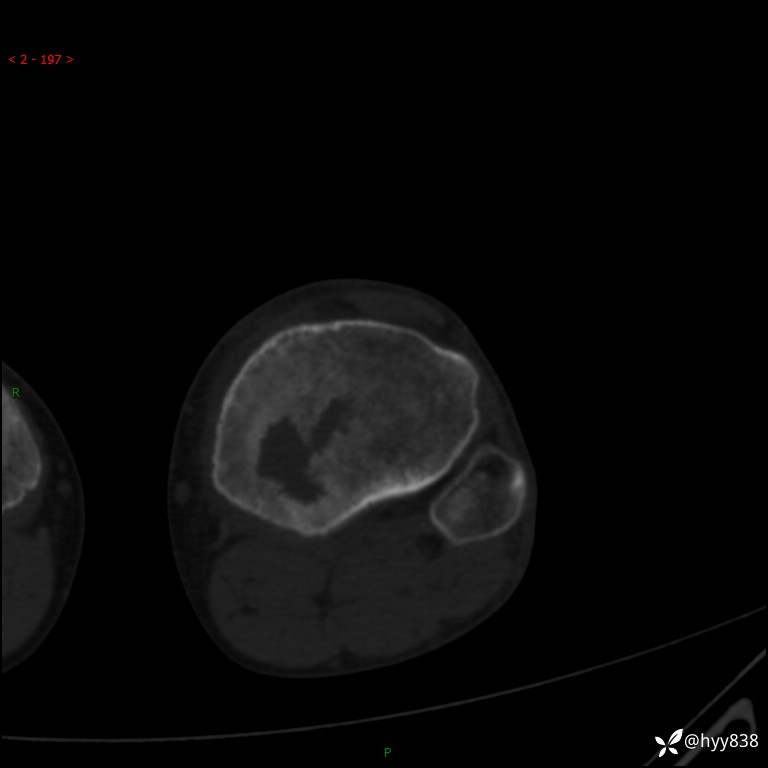

CT

干骺端溶骨性病变病灶周广泛水肿